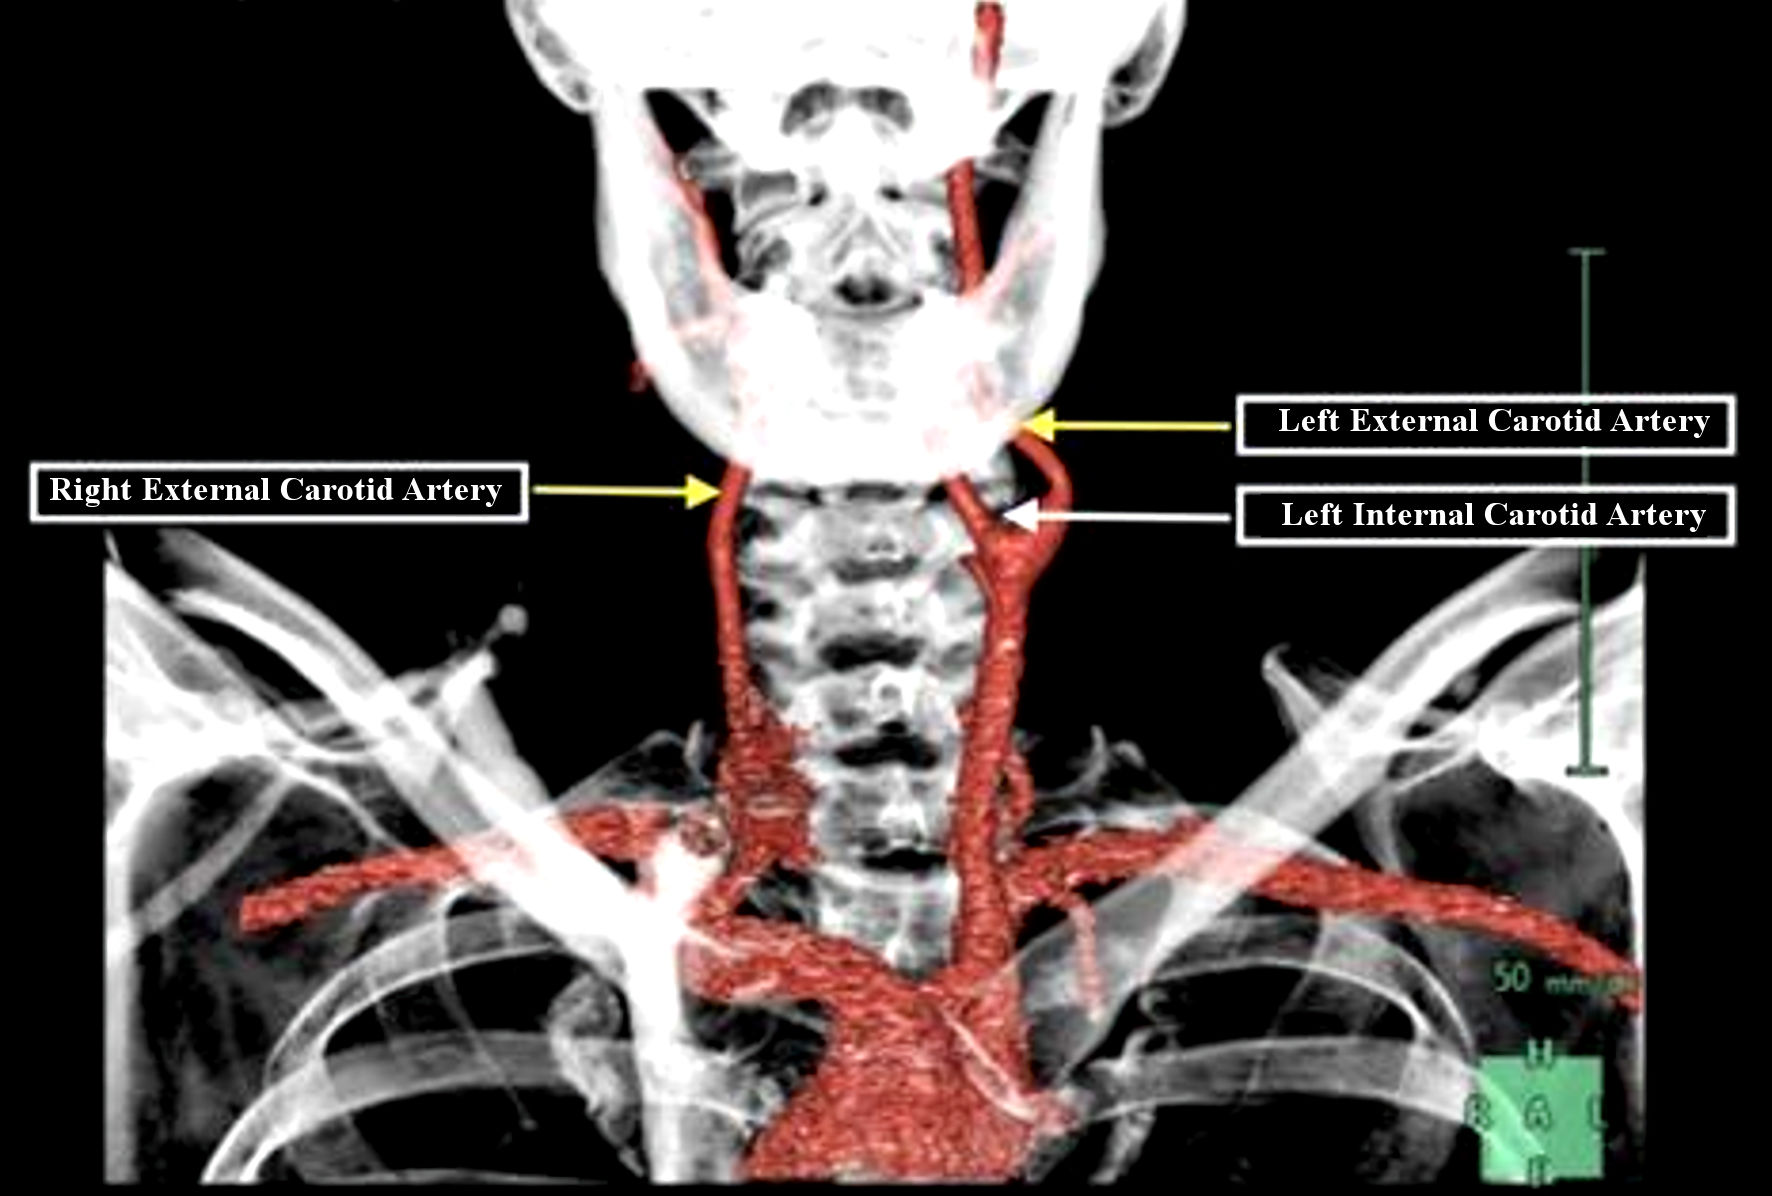

Carotid Artery Stenosis Wikidoc

https://www.wikidoc.org/images/7/7a/Carotid-artery-stenosis-001.jpg

Carotid Artery Stenosis Wikidoc

Occluded Carotid Artery Carotisverengung Swiss Surgery